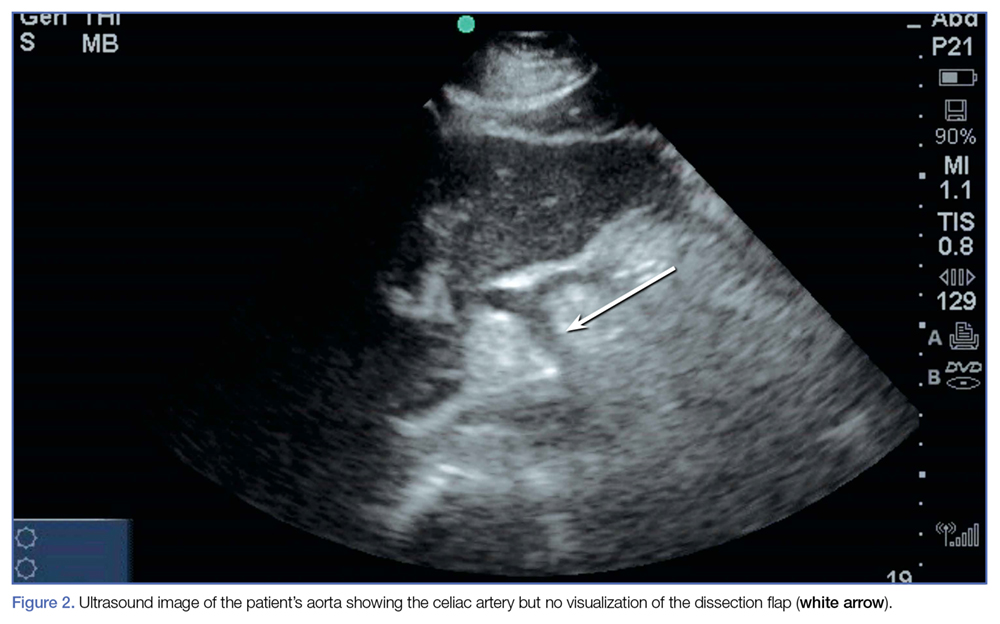

Despite the excellent views taken of the aorta, celiac trunk, and hepatic and splenic arteries (Figure 2), the dissection was not visible on either of the two ultrasound images.In the MICU, the patient’s BP was stabilized on hospital day 2, and he was transitioned to oral antihypertensive medications. He was also started on a heparin infusion at the recommendation of vascular surgery services.